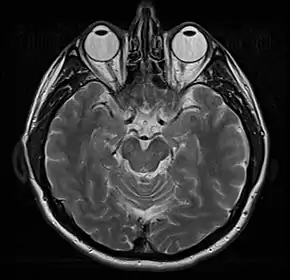

Normal axial T2-weighted MR image of the brain

- T2-weighted (T2W) images: CSF is light, but fat (and thus white matter) is darker than with T1. T2-weighted images are useful for visualizing pathology.[26]